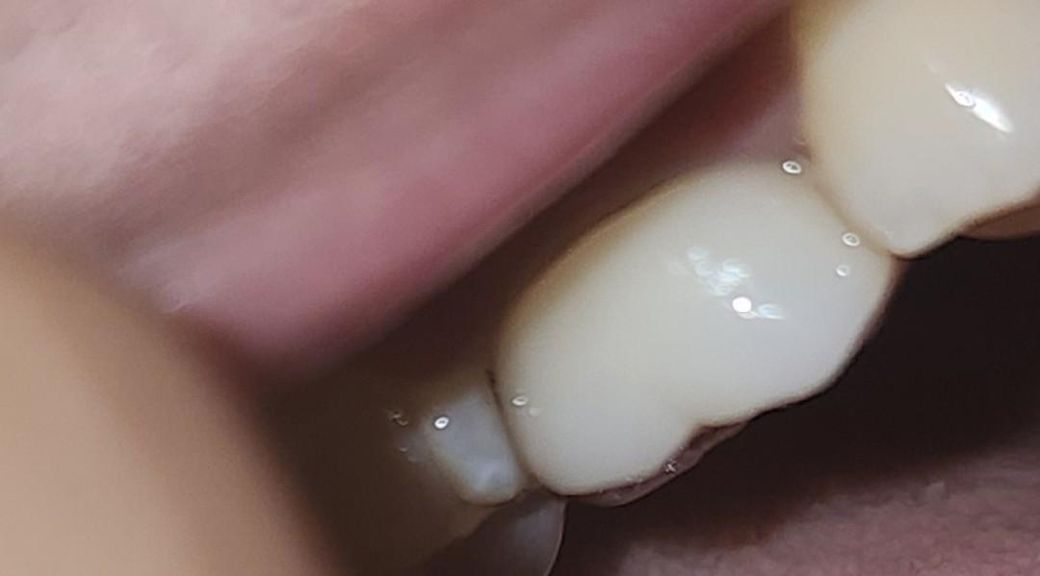

• 3번 째 사진